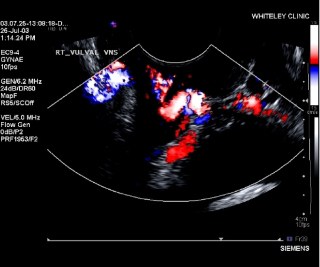

Trans-vaginal Duplex Ultrasound (TVS)

When ovarian or pelvic vein reflux is suspected, or vulval varicose veins have been seen, or when varicose veins appear in the legs behind the Adductor Longus tendon, a specialised Ultrasound examination is required.

The veins in the pelvis cannot be seen easily by ultrasound across the abdomen – as they are too deep.

Therefore, we use a special ultrasound probe that can see the veins through the vagina.

Our specialist female vascular scientists perform this test and can check if there are varicose veins in the pelvis – and if there are – where they are coming from.

Although most do come from the ovarian veins (as described before) there are other veins in the female pelvis that can also cause the same thing – the internal iliac veins.

The scientists can show the patient what is happening as they carry out the scan – and then they write a detailed report so that the consultants can try to plan appropriate treatment.